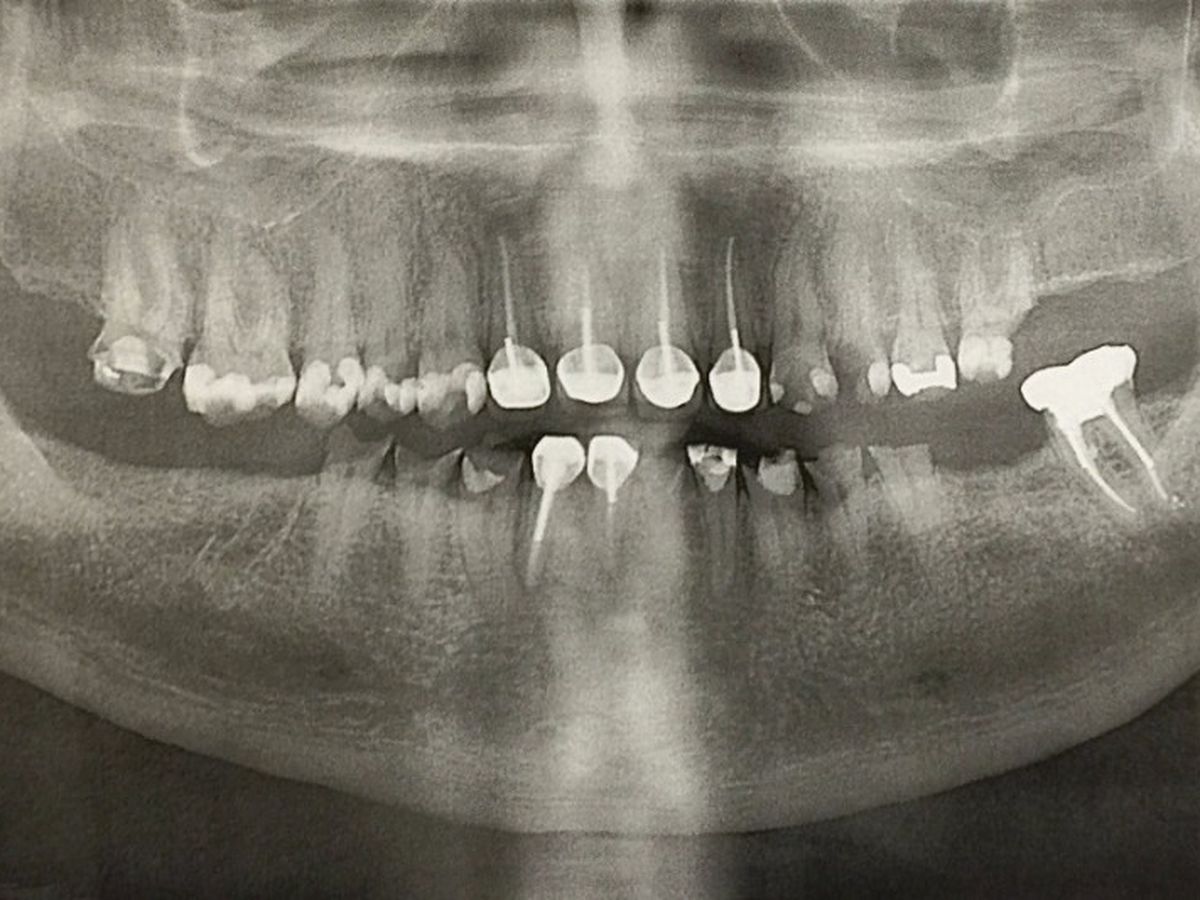

My name is Kristen Boland and I am starting this Go Fund me for my husband Shawn Boland because he not someone who would ever ask for help for himself. Shawn served in the United States Coast Guard from 2000-2005. He was stationed in Gloucester, Ma. on board a 110' patrol boat for 2 years, (He was there during the "Perfect Storm"). After Gloucester he went to the Coast Guard Station in Bodega Bay, Ca. driving the search & rescue boats for 3 years. During his time serving in the Coast Guard he suffered constantly from sea sickness. He told me that although he learned to be functional and do his job he never got over the nausea and vomiting. As a result the stomach acid quickly wore the enamel off of his teeth and started a process of erosion to the point that his teeth started to break and chip. He went to the Coast Guard dentist while he was still in and was told that there was nothing they could do about it. He recently spoke with the VA and was told that it is a very long process but also next to impossible to specifically get help with teeth. Over the years I have seen him suffer greatly with abscesses, root canals, broken teeth, extractions and difficulty eating. He has spoken with his dentist & oral surgeon and the only option is to remove all the remaining teeth. Then implants would be put in. Although we have double dental insurance we are told it will cost us about $60,000 out of pocket. Because of this, Shawn has put off starting this process for far too long because he feels guilty about putting his family, me and our two kids Shamus & Maisie, into that much debt. We have encouraged him to get the process started no matter the cost but he continues putting it off because of the financial burden.

It has now got to the point that it is causing more serious health issues. He has a swollen lymph node on the left side of his neck that won't heal because of the bacteria from his damaged teeth and recently the left side of his face swelled up and went partially numb and he had to have an emergency extraction to fix that. He has been having heart palpitations that his doctor cannot yet explain and we don't know if it is related to his teeth situation or not. Both his regular doctor & an ear-nose-throat specialist have said that this process needs to happen sooner rather than later. I am scared and I know he is too, so this go fund me is the only thing I could think of to help get this process started as quickly as possible and hopefully relieve his pain and some of the stress caused by trying to come up with $60,000 in a hurry. Shawn is an amazing husband and father, he works hard doing 12 hour shifts as a maritime dispatcher and drives 80 miles one way to get to work to support his family. I feel that after 5 years of going through seasickness and serving his country and saving lives he deserves to stop feeling anxiety and embarrassment about his teeth, to be able to eat normal food and to be healthy and not in pain all the time. I will be so glad to see him finally getting this problem taken care of and I know he will be so incredibly grateful for any help to make this happen. We are fully committed to doing this one way or another so that he'll be healthy and around for us for a long time to come. We are grateful for any help however small. Thank you everyone for taking the time to read this.

It has now got to the point that it is causing more serious health issues. He has a swollen lymph node on the left side of his neck that won't heal because of the bacteria from his damaged teeth and recently the left side of his face swelled up and went partially numb and he had to have an emergency extraction to fix that. He has been having heart palpitations that his doctor cannot yet explain and we don't know if it is related to his teeth situation or not. Both his regular doctor & an ear-nose-throat specialist have said that this process needs to happen sooner rather than later. I am scared and I know he is too, so this go fund me is the only thing I could think of to help get this process started as quickly as possible and hopefully relieve his pain and some of the stress caused by trying to come up with $60,000 in a hurry. Shawn is an amazing husband and father, he works hard doing 12 hour shifts as a maritime dispatcher and drives 80 miles one way to get to work to support his family. I feel that after 5 years of going through seasickness and serving his country and saving lives he deserves to stop feeling anxiety and embarrassment about his teeth, to be able to eat normal food and to be healthy and not in pain all the time. I will be so glad to see him finally getting this problem taken care of and I know he will be so incredibly grateful for any help to make this happen. We are fully committed to doing this one way or another so that he'll be healthy and around for us for a long time to come. We are grateful for any help however small. Thank you everyone for taking the time to read this.